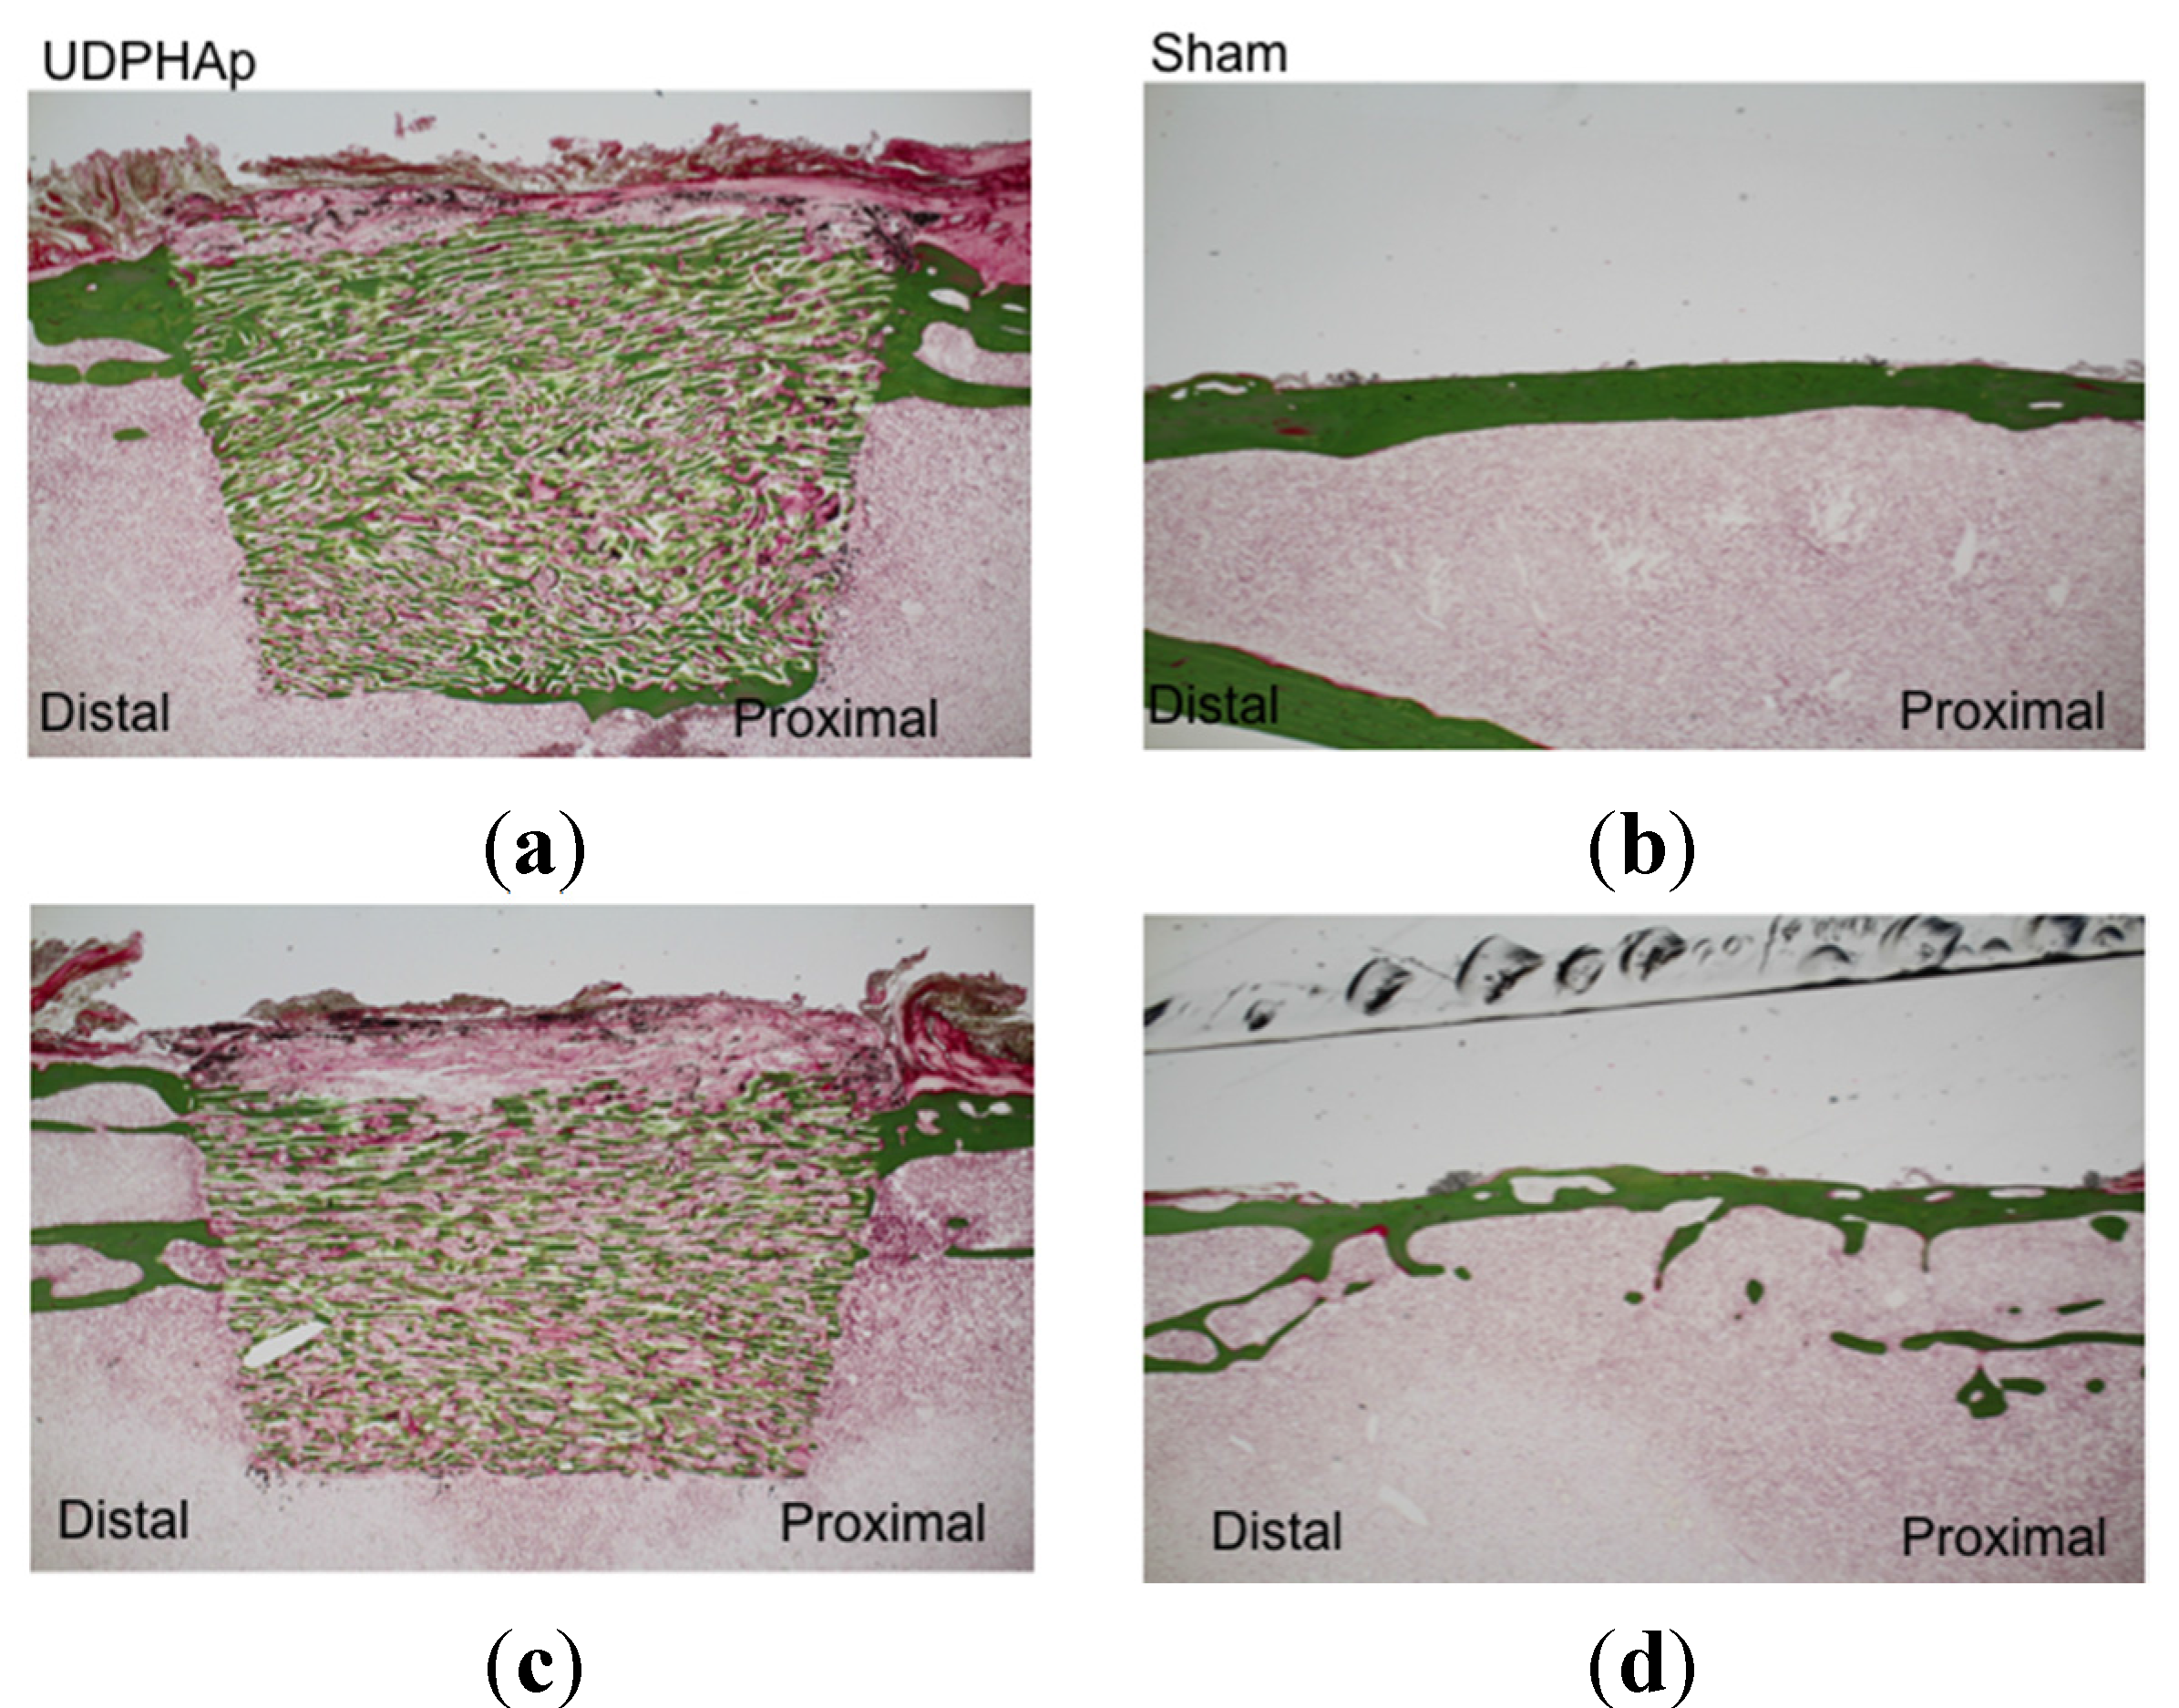

2. Results and Discussion

3.3. Bone Formation in Cortical and Medullary Bone Regions